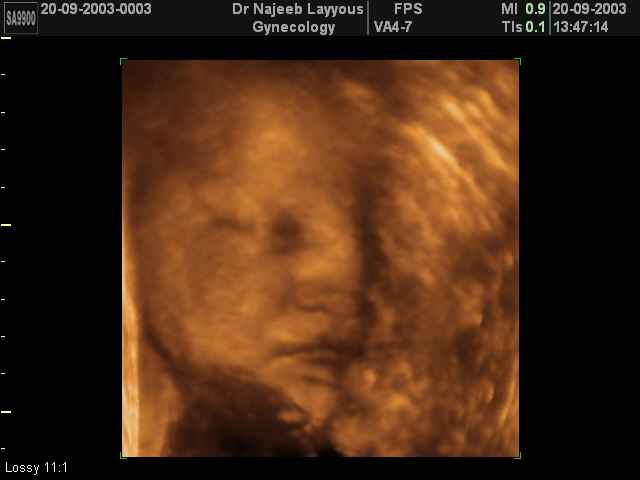

- Fetal Behavior Ultrasound Photos

Ultrasound Photos in 3D showing Fetal Behavior Inside the uterus | Dr N Layyous